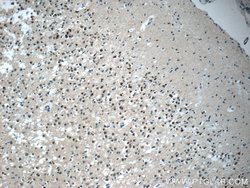

| Applications | Immunohistochemistry (Paraffin), Western Blot |

This KIAA0087 antibody gives a 40 kDa band in Western Blot.

KIAA0087 (KIAA0087 LncRNA) is an RNA Gene, and is affiliated with the non-coding RNA class. Diseases associated with KIAA0087 include Endometrial Cancer and Pancreatic Cancer.Specifications